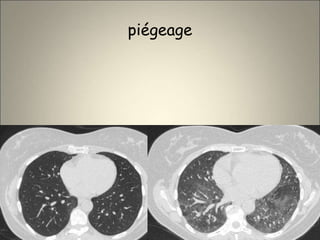

• Représentée essentiellement par le piégeage expiratoire

Zones de basse densité +/- étendues (≥ 1segment

,sauf le segment de FOWLER ),observées sur les coupes

expiratoires (a comparer aux coupes inspiratoires ++)

Peut être physiologique (50% chez sujets

asymptomatiques ,↗ avec âge et tabac )

N’est pas spécifique

Peut être quantifié avec précision

S.MATSUOKA J. COM. ASS. TOM. 2007

piégeage